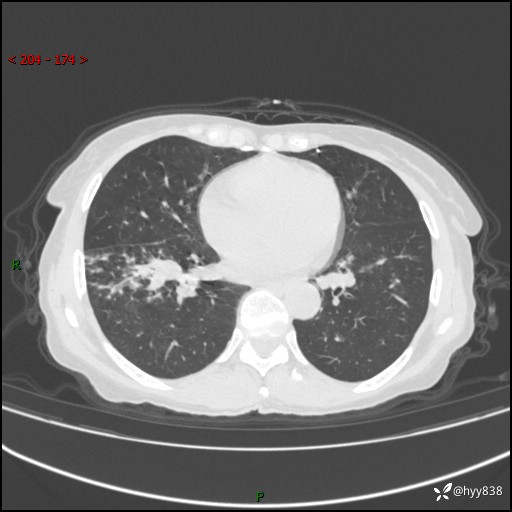

患者性别:男

患者年龄:69岁

简要病史:咳嗽咳痰2月,夜间加重

辅助检查:CT

临床诊断:感染

胸部CT平扫